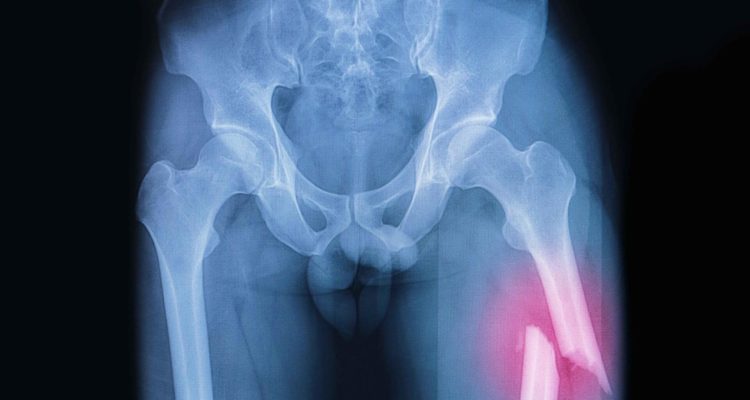

Переломи хребців і кальциноз черевної аортою можуть бути візуалізовані за допомогою одного і того ж методу.

Нове дослідження, в якому взяли участь 5365 літніх чоловіків, показує, що кожен з цих показників пов’язаний з більш високим ризиком розвитку переломів стегна та інших переломів.

Дослідники виявили, що включення обох показників, а не тільки одного, покращує здатність передбачати, у яких чоловіків з найбільшою ймовірністю трапиться перелом стегна або інший перелом в майбутньому.

“І кальциноз черевної аорти, і перелом хребця можна одночасно і швидко виявити на стандартних рентгенограмах або зображеннях щільності латеральної кістки хребта, і це може допомогти в оцінці ризику перелому у літніх чоловіків, у яких є один або обидва фактори ризику”, – розповідає провідний автор доктор Джон Т. Шоусбо з Університету Мінесоти.